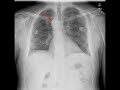

Right Aortic Arch

This is a patient who presented to the emergency department with a cough. A frontal radiograph of the chest was obtained. When evaluating the contours of the mediastinum, this patients aortic arch is on the right. There is no evidence of a typically identified mediastinal mogul in the expected location of an anatomic left-sided aortic arch. This patient has a variant right-sided aortic arch without additional anomalies. Right sided aortic arches can be seen without or without mirror branching of the great vessels. When patients do not have mirror branching, there a typically no associated cardiac defects. Mirror branching with a right-sided arch is associated with a high incidence of additional cardiac anomalies.